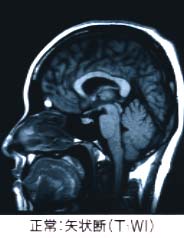

中枢神経とは下図の如く、脳(大脳・小脳・脳幹)・脊髄よりなります。

人の脳・脊髄の模式図 人の脳のMRI画像